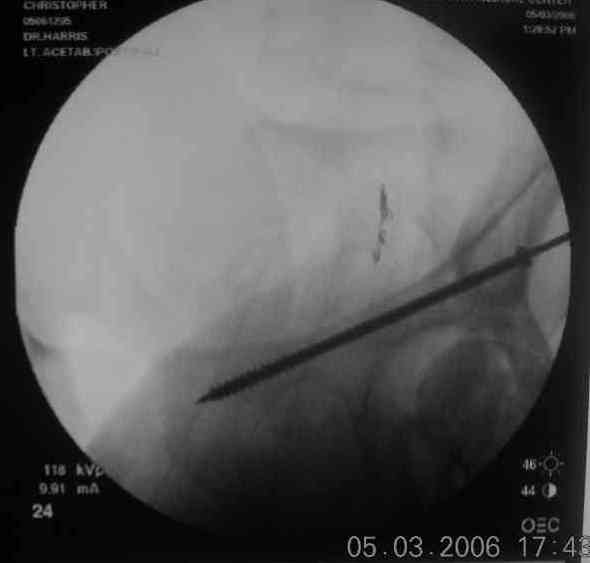

For this fracture pattern, I have had good luck with fluoro guided anterior column screw first.

pt supine helps get the best fluoro images. then cut the guide wire below the skin and leave it in place along with the anterior column screw. staple the small incision closed and cover with ioban. then reposition, remove ioban, reprep/drape pt in lateral decub for KL approach.

sometimes the anterior column screw needs to be backed out to help get the best reduction of posterior column. with guide wire in place this is fairly easy, the fracture will rotate around the wire, and the anterior column screw can be readvanced with confidence it is within bone. I have intra-op photos on office computer if interested.